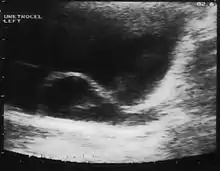

Since the advent of the ultrasound, most ureteroceles are diagnosed prenatally. The pediatric and adult conditions are often found incidentally, i.e. through diagnostic imaging performed for unrelated reasons.

IVU-shows Adder head appearance or Cobra head appearance. Cystoscopy-shows translucent cyst which is thin walled surrounding ureteric orifice